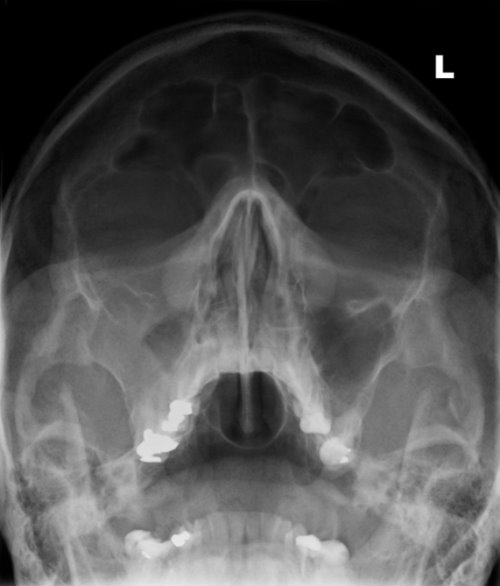

Poskiontelotulehdus oikealla

Kuva 1.

Poskiontelotulehdus oikealla. Kuutamokuva: oikeassa poskiontelossa runsas limakalvoturvotus sinuiitin merkkinä. Vrt. normaali sinusröntgenlöydös «Normaali sinusröntgenlöydös»1

.

Kuva: Tatu Kemppainen